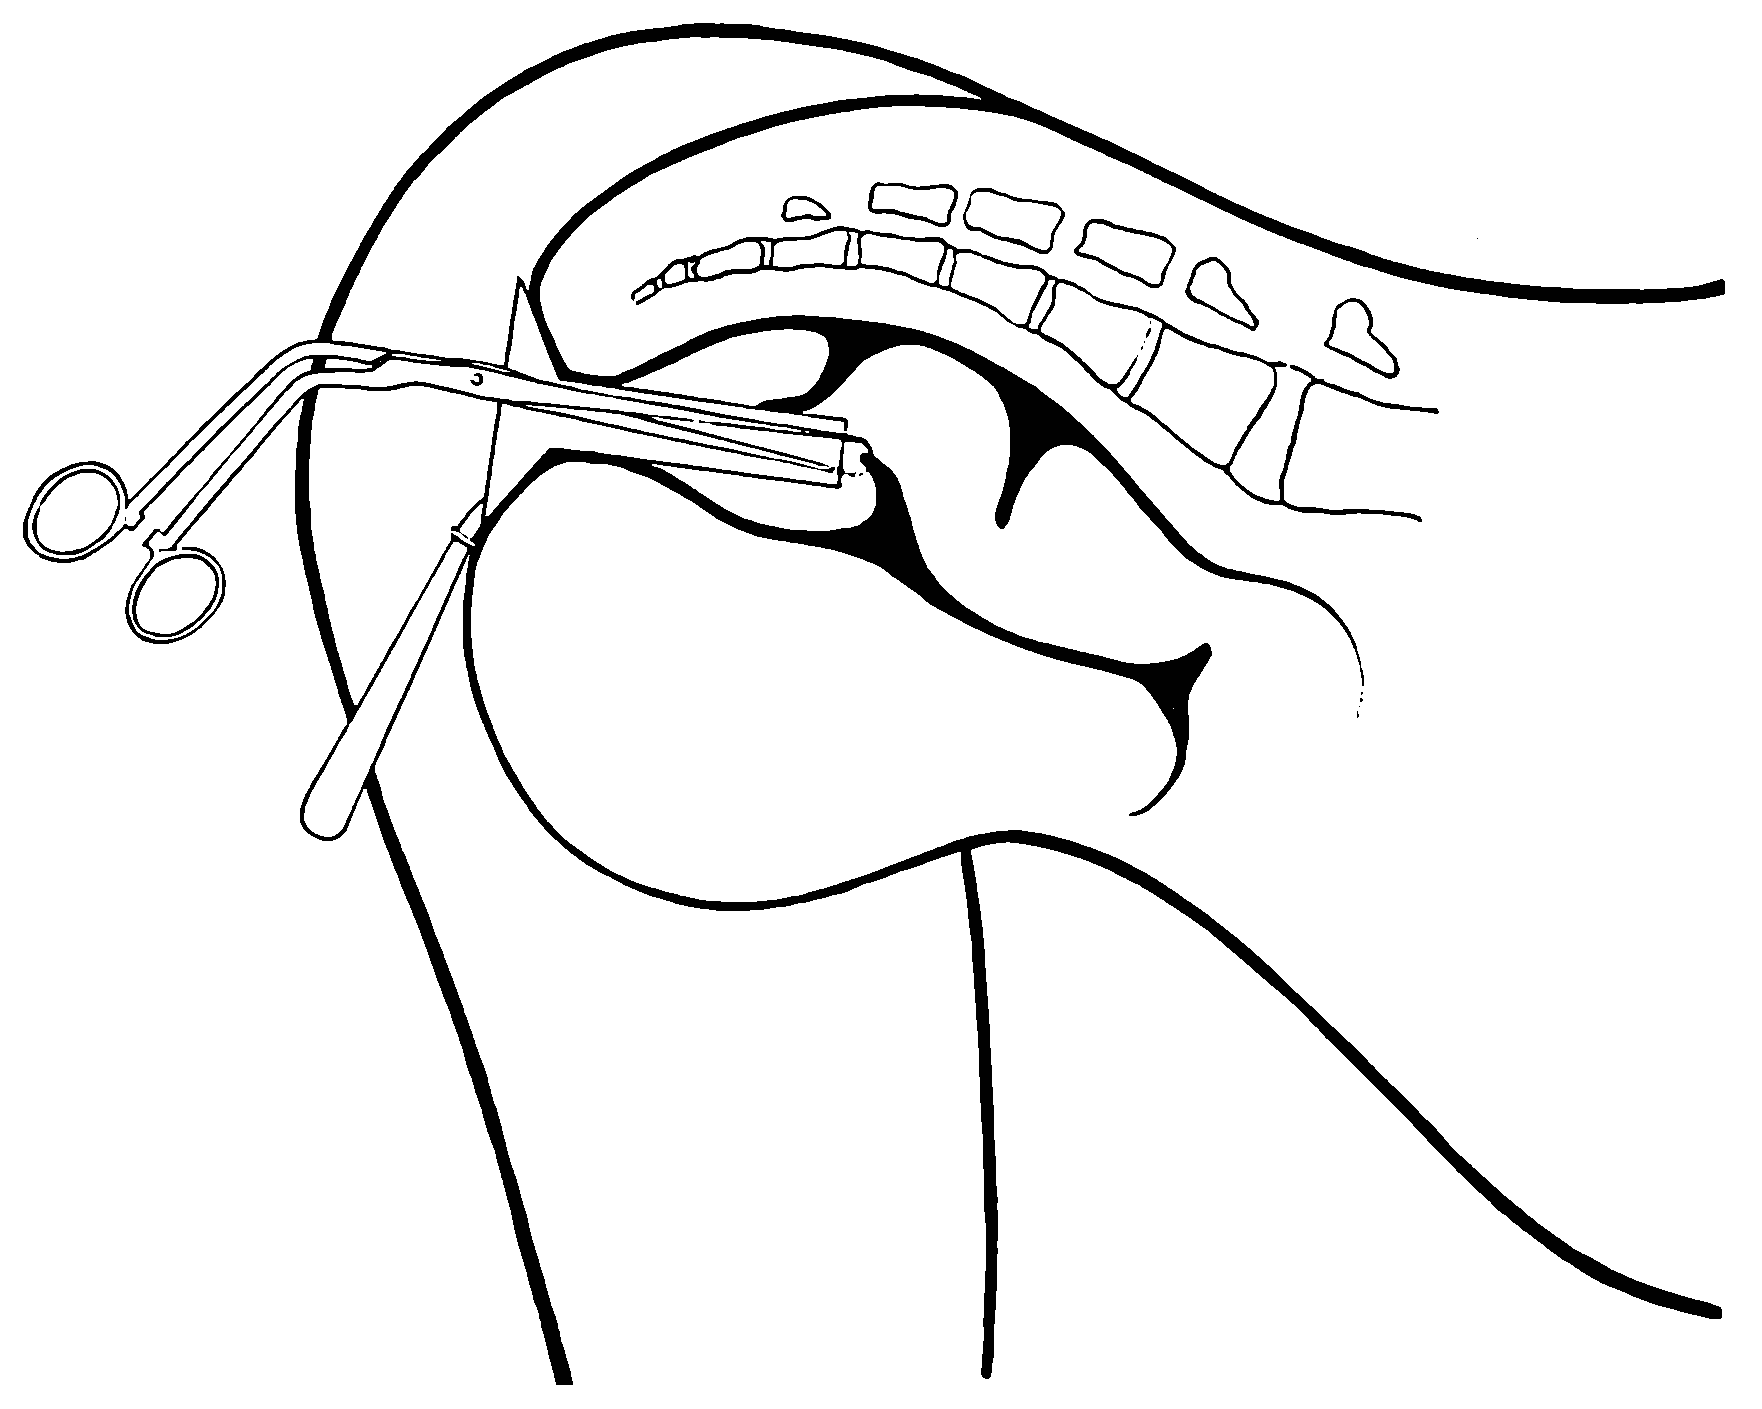

Fig. 17.—The hook for testing the valves.

Stricture of the rectum need no longer be regarded as of only doubtful presence, and this method proves positively, even to the casual observer, how fallacious is the method of rectal sounding usually employed for the diagnosis of stricture. I have repeatedly proved to visitors how easy it is for an entering or returning bulb-sound to be caught and held by the rectal valves,[14] and thereby yielding signs generally considered diagnostic of organic stricture of the rectum.

Passing the finger beyond the borders of the levator ani, the distal phalanx enters the movable or abdominal rectum, where it may be hooked over the pelvic floor. In some instances, if the finger be directed backward and crowded with a boring maneuver through the loose folds of the movable rectum, and[59] provided the folded knuckles displace upward the pelvic floor, the finger may be made to engage the lowermost of the rectal valves, which will contract about the finger with a rhythmic action and mislead the uninformed, inexperienced and undiscriminating explorer to think that he is but now encountering the ental sphincter muscle, or, perhaps, that he has discovered a stricture—the phantom stricture? In the passive rectum, this valve is usually about three inches (7.62 cm.) above the lower border of the ental sphincter muscle. The great range of mobility of the pelvic diaphragm permits a finger of two inches (5.08 cm.) length to be hooked over a valve which under some circumstances may be an inch and a half (3.81 cm.) beyond its reach.